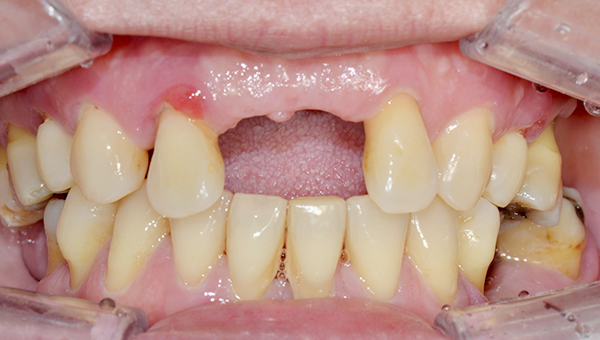

치료사례임플란트

강*란 임플란트 시술 사례

전체 임플란트

2025.02.07

치료 전

2025.08.19

치료 후